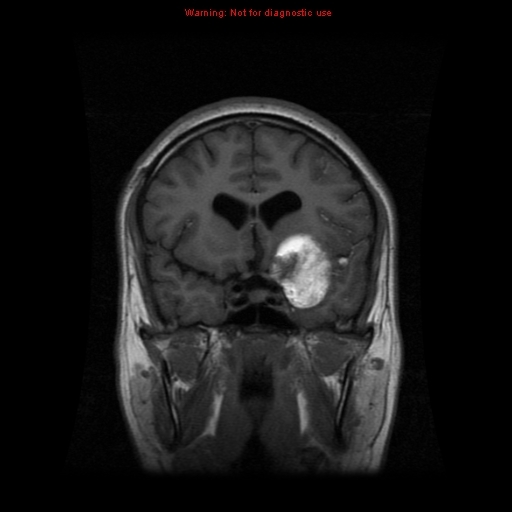

There is a well defined, brilliantly enhancing round lesion is noted in the left lung suggestive of pulmonary arteriovenous malformation.

Incidentally noted a large haemangioma is the superior segments of liver.

Imaging features are most likely suggestive of Osler-Weber-Rendu syndrome.

Hereditary haemorrhagic telangiectasia

Hereditary haemorrhagic telangiectasia (HHT), also known as Osler-Weber-Rendu syndrome, is a rare inherited disorder characterised by abnormal blood vessel formation in the skin, mucous membranes, and organs including the lungs, liver, and central nervous system.

It is an autosomal dominant multi-organ vascular dysplasia, characterised by multiple arteriovenous malformations (AVMs) that lack an intervening capillary network. Telangiectasias (small superficial AVMs) are particularly common. Mutations have been found in one of several genes (three known so far). De novo mutations are rare, almost all have a first-degree relative affected.

CNS: 5-10%

cerebral AVMs, spinal AVMs or cerebral aneurysms

complications: headache, seizures, paraparesis, haemorrhage

one-third of cerebral complications in HHT are due to cerebral AVMs or aneurysms, and two-thirds are due to paradoxical emboli from pulmonary AVMs

increased incidence of capillary telangiectasia and developmental venous anomalies

CNS

MR: cerebral and cerebellar AVMs typically in superficial locations